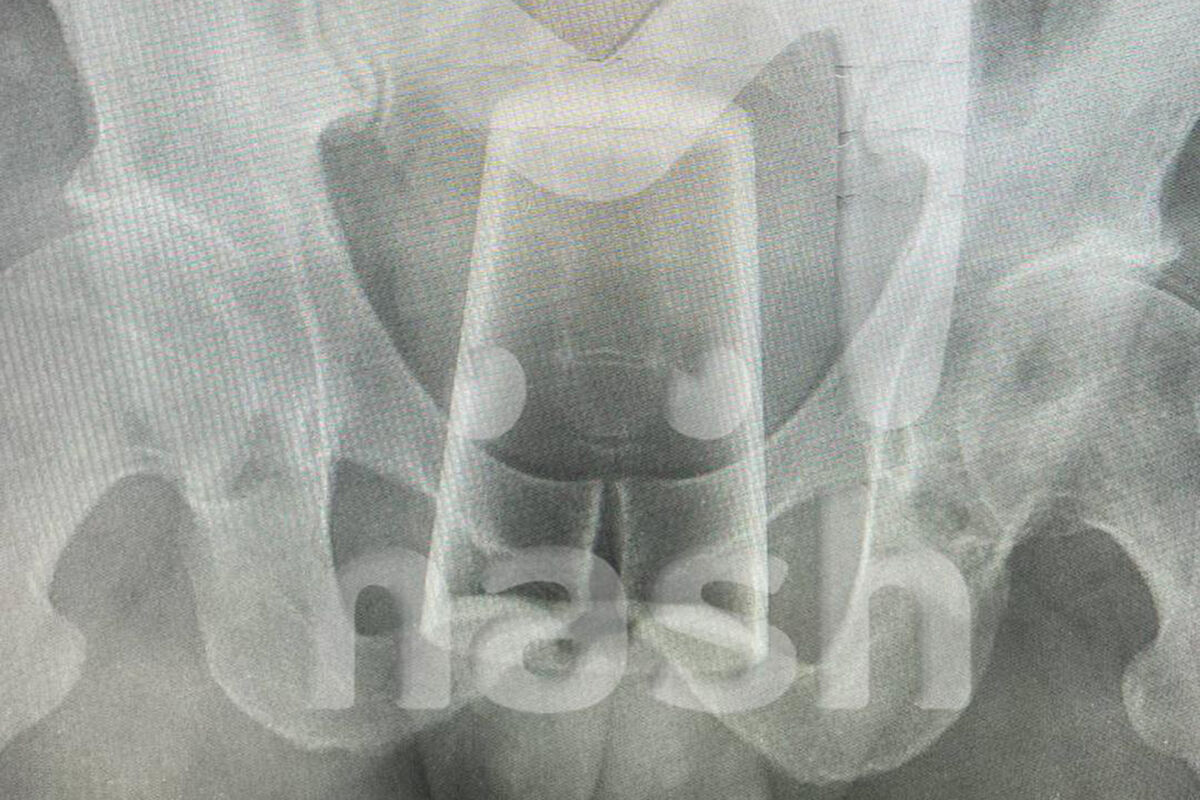

В Уфе мужчина попал в больницу со стаканом в заднем проходе после конкурса на 23 февраля. Об этом сообщает Telegram-канал Mash.

Инцидент произошел в День защитника Отечества, когда двое друзей отмечали праздник. По словам пострадавшего, они с товарищем выпили, закусили и решили устроить конкурс. Однако в какой-то момент он поскользнулся и нечаянно упал на стакан, после чего тот оказался у него в заднем проходе.

Попытки самостоятельно вытащить инородное тело не увенчались успехом — пострадавшему вызвали медиков. Позже врачи извлекли стакан из заднего прохода мужчины и отпустили его домой, порекомендовав регулярно наблюдаться у специалистов после случившегося.